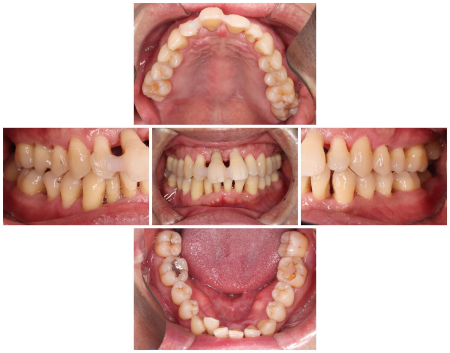

治療中

まず、歯ぐきの内側を清掃する「縁下スケーリング」と、歯ぐきを開いて歯の根を直接見ながら綺麗にする「フラップ手術」を行い、上の前歯のプラークや歯石、感染物を徹底的に取り除きました。

その後、歯に専用のパウダーを吹き付ける「エアーフロー」によるクリーニングを2週に1回の頻度で行い、出血のない歯ぐきを目指しました。

歯ぐきの回復が認められた段階で前歯を確認した結果、特に揺れが強かった右上の前歯1本以外は残せると判断しました。

そこで、温存が難しい歯を抜いてから、その隣の右上の前歯1本(側切歯/2番)と左上の前歯2本(中切歯、側切歯)を連結して橋渡しのように歯を補う被せ物「ブリッジ」で治療する方法をご案内し、ご希望いただきました。

被せ物治療の際は、歯を1本ずつ丁寧に削って土台の形に整え、まずは1段階目の仮歯を装着しました。

土台の形を微調整した後、口腔内の写真撮影と型取りを行い、患者様のご希望を考慮した形の本格的な仮歯を再度作製しました。

口腔内で仮歯の調整を重ねて理想的な形に仕上げてから、お顔の写真撮影や歯の色合わせ「シェードテイク」および本歯用の型取りを行いました。